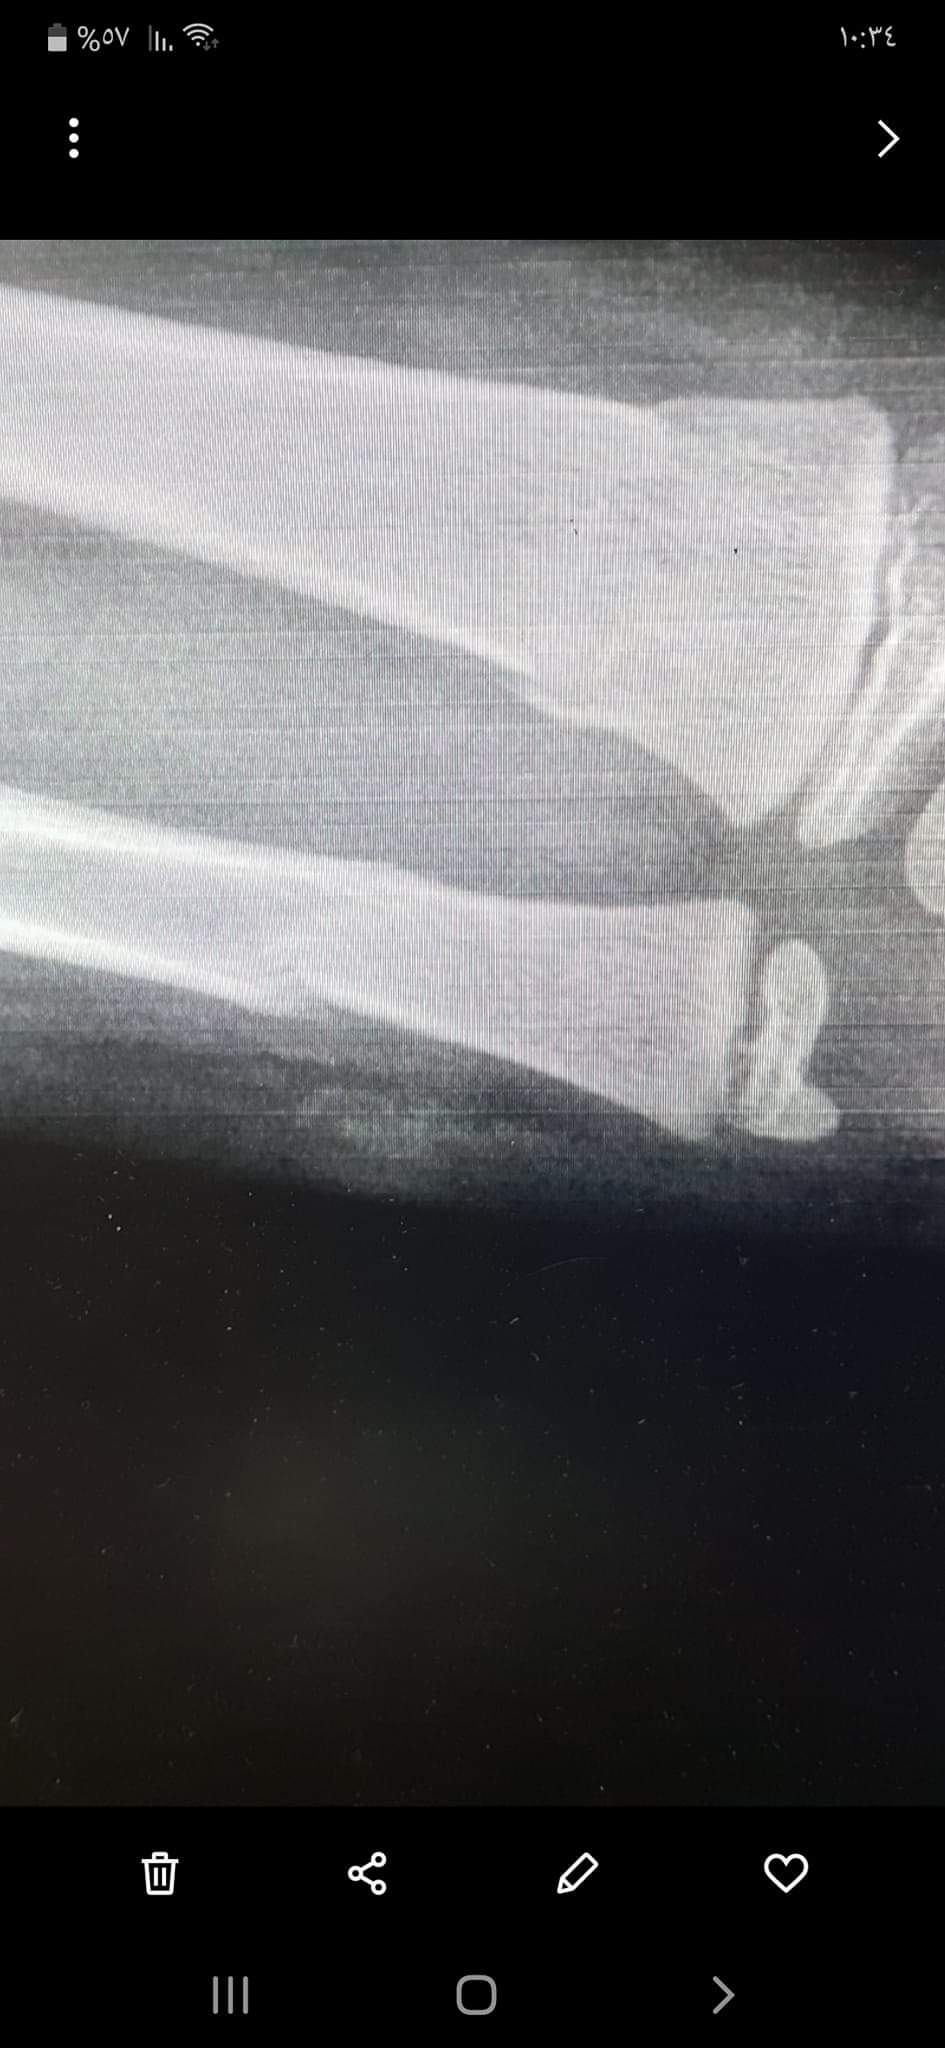

نبأ الأردن-تعرض الطفل خطاب أحمد الوشاح لهجوم من كلب ضال وشرس مساء أمس الاثنين في منطقة السلط المغاريب، مما تسبب له بكسرين في يده.

وذكر والد الطفل أحمد الوشاح لموقع نبأ الأردن الإخباري أن الطفل الذي يبلغ 8 سنوات كان يقف أمام البيت ومن ثم هوجم من قبل الكلب وتم تخلصيه من بين فكي الكلب ونقله الى المستشفى، ووصف حالة ابنه بالخطيرة بسبب تمزق في الأنسجة بيده.